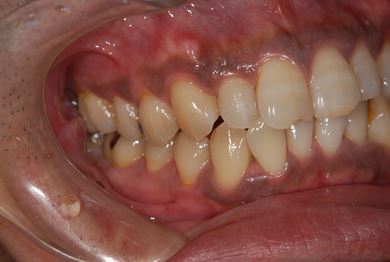

セラミック治療+歯肉歯槽骨整形術

| 性別/年齢 | 男性 / 45歳 | ||||||||||||||||||||||||||||||||

| 主訴 | 詰め物をしている歯が割れてしまったので、治療して欲しい。 | ||||||||||||||||||||||||||||||||

| 治療方針 | セラミック治療にて、審美的回復を行う。 | ||||||||||||||||||||||||||||||||

| 治療内容 | メタルボンドセラミッククラウン1本(メタルボンドセラミック用土台1本)、歯肉歯槽骨整形手術 | ||||||||||||||||||||||||||||||||

| 総治療費 | 157,185円 | ||||||||||||||||||||||||||||||||

| 治療期間 | 7ヶ月 |